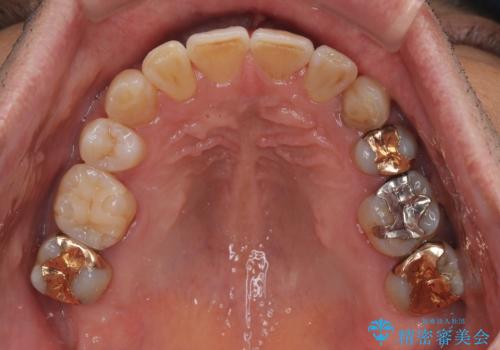

銀歯やむし歯治療されている歯を抜歯する治療計画としたため、やや時間はかかりましたが、治療後の仕上がりには大変満足していただけました。

- 治療期間

- 3年4ヶ月

- 治療回数

- 30回以上